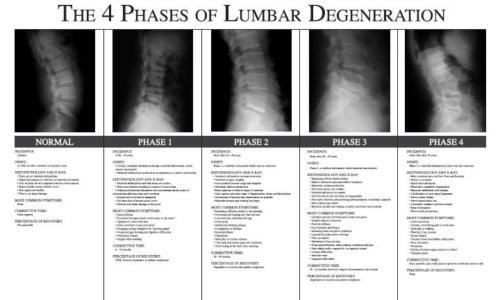

Chiropractic phases of Lumbar degeneration poster